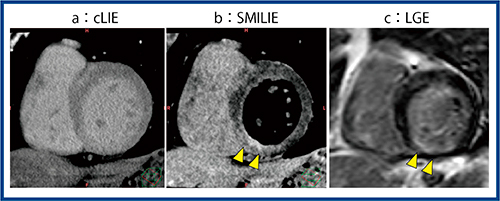

心筋のviability評価は従来,核医学検査(心筋血流SPECT)とMRI(遅延造影:LGE)が用いられており,感度の高さからMRIがゴールドスタンダードと言われている。心臓CTでもヨード造影剤がLGEと同様の挙動を示すことから,viability評価が可能と考えられるが,コントラストの低さが課題となっていた。われわれは,遅延相から冠動脈相をサブトラクションして,遅延造影画像を得るSMILIEという手法を開発して評価を行っている(図1)。

図1 SMILIEの原理

(RSNA 2015で発表)

1.SMILIEの作成方法

SMILIEは,遅延相の撮影画像から冠動脈相の画像をサブトラクションして得られるが,この時に非剛体位置合わせ処理を行うことでミスレジストレーションの少ない差分画像を得ることができるのが特長である。MRIのLGEで50%以上のtransmuralityがある心筋梗塞の部位を,SMILIEと従来の遅延相(conventional LIE:cLIE)で比較したところ,SMILIEではLGEとほぼ同等の検出能があるという結果が得られた(AUC:0.985)。

症例1(図3)は,下壁の心筋梗塞疑い。冠動脈CTで右冠動脈に90%狭窄を認め,陳旧性心筋梗塞(OMI)と考えられた。cLIEの画像(図3 a)では造影効果ははっきりしないが,SMILIE(図3 b)では下壁の内膜側に遅延造影効果が認められた。MRI(LGE:図3 c)でも同様でtransmuralityは50%未満であり,バイアブルと判断され治療が行われた。

図3 症例1:左室肥大,心筋梗塞疑い